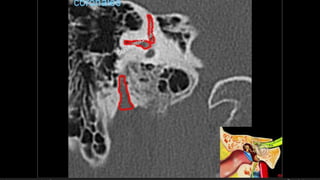

Evaluación Imagenologica

• #38 Izqu. AXIAL-- fxLongitudinal perdonan la capsula otica (laberinto oseo) Centro AXIAL fx trnasversa lascuales tperdonan el lab erinto oseo Dere: MIXTA – tmp perdona